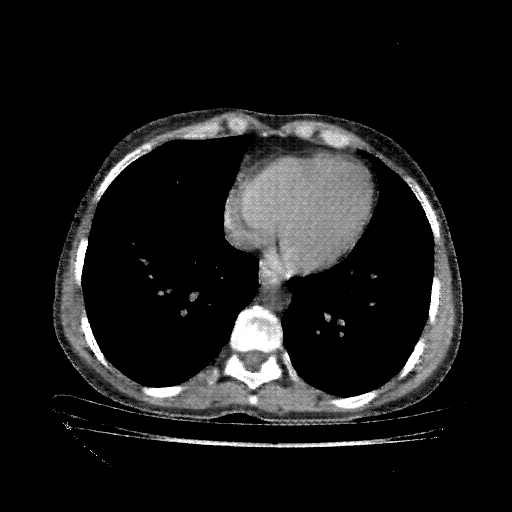

Image Grid

4×3 grid: Rows show different image types (Original NATIVE, Reconstructed NATIVE, Original VENOUS, Generated VENOUS), Columns show windowing techniques (No Window, Lung Window, Mediastinum Window)

Original NATIVE CT scan (input)

No window - Raw intensity values

Original VENOUS CT scan

No window - Raw intensity values

Generated VENOUS CT scan (A→B translation)

No window - Raw intensity values

Windowing Parameters

- No Window: Raw intensity values without windowing

- Lung Window: WL -600, WW 1500 → Low −1350, High +150 (optimal for pulmonary structures)

- Mediastinum Window: WL 40, WW 400 → Low −160, High +240 (optimal for soft tissues)